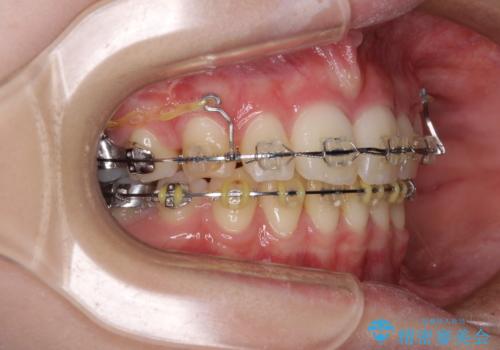

治療途中で転院 抜歯矯正の仕上げ治療

- 地元で抜歯治療を行っている途中、東京へ転職したため治療を継続して欲しいとのことで来院された患者様です。

出っ歯を抜歯矯正にて治療をしていらっしゃいましたが、抜歯スペースが少し残っていたため、閉じて歯列を仕上げていくこととしました。